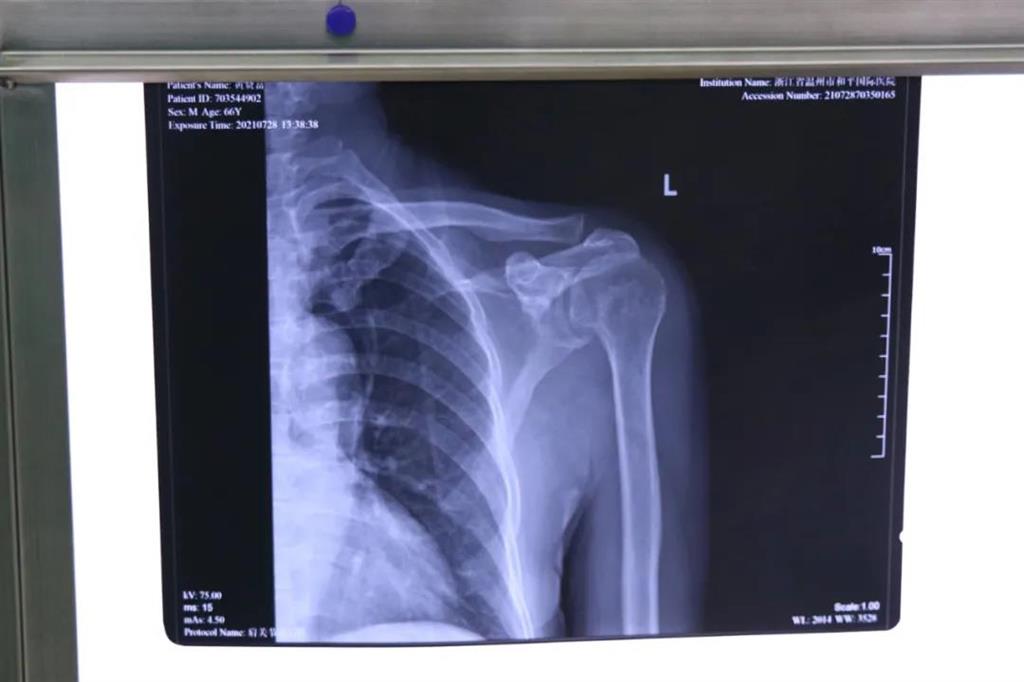

患者黃大叔(66歲)為"左肩袖損傷"病人,8年來左肩部持續疼痛伴肩關節活動輕微受限?;颊哂诮谧蠹绮刻弁醇又?,抬肩困難,難以完成穿衣服等日常生活活動。

術前檢查見左肩關節輕度腫脹,左肩關節岡上肌附著處壓痛明顯,MRI提示左岡上肌肌腱斷裂回縮,岡下肌腱部分撕裂。為此和平國際醫院關節鏡微創團隊為患者制定了詳細的一期、二期手術方案。此次手術為一期肩袖成形術。

常規手術方式是傳統切開肩袖縫合術,但缺點就是創傷較大,切口較大,術后康復困難,視野較小,難以處理其他合并傷。目前更先進的技術是采取肩關節鏡微創手術,術中探查肩袖撕裂口,并將其縫合固定。

在和平國際醫院關節鏡微創團隊的協作下,手術順利,成功用微創肩關節鏡進行肩袖修補術。術中、術后患者幾無出血,且手術切口小,美觀,患者左肩部疼痛得到明顯緩解。